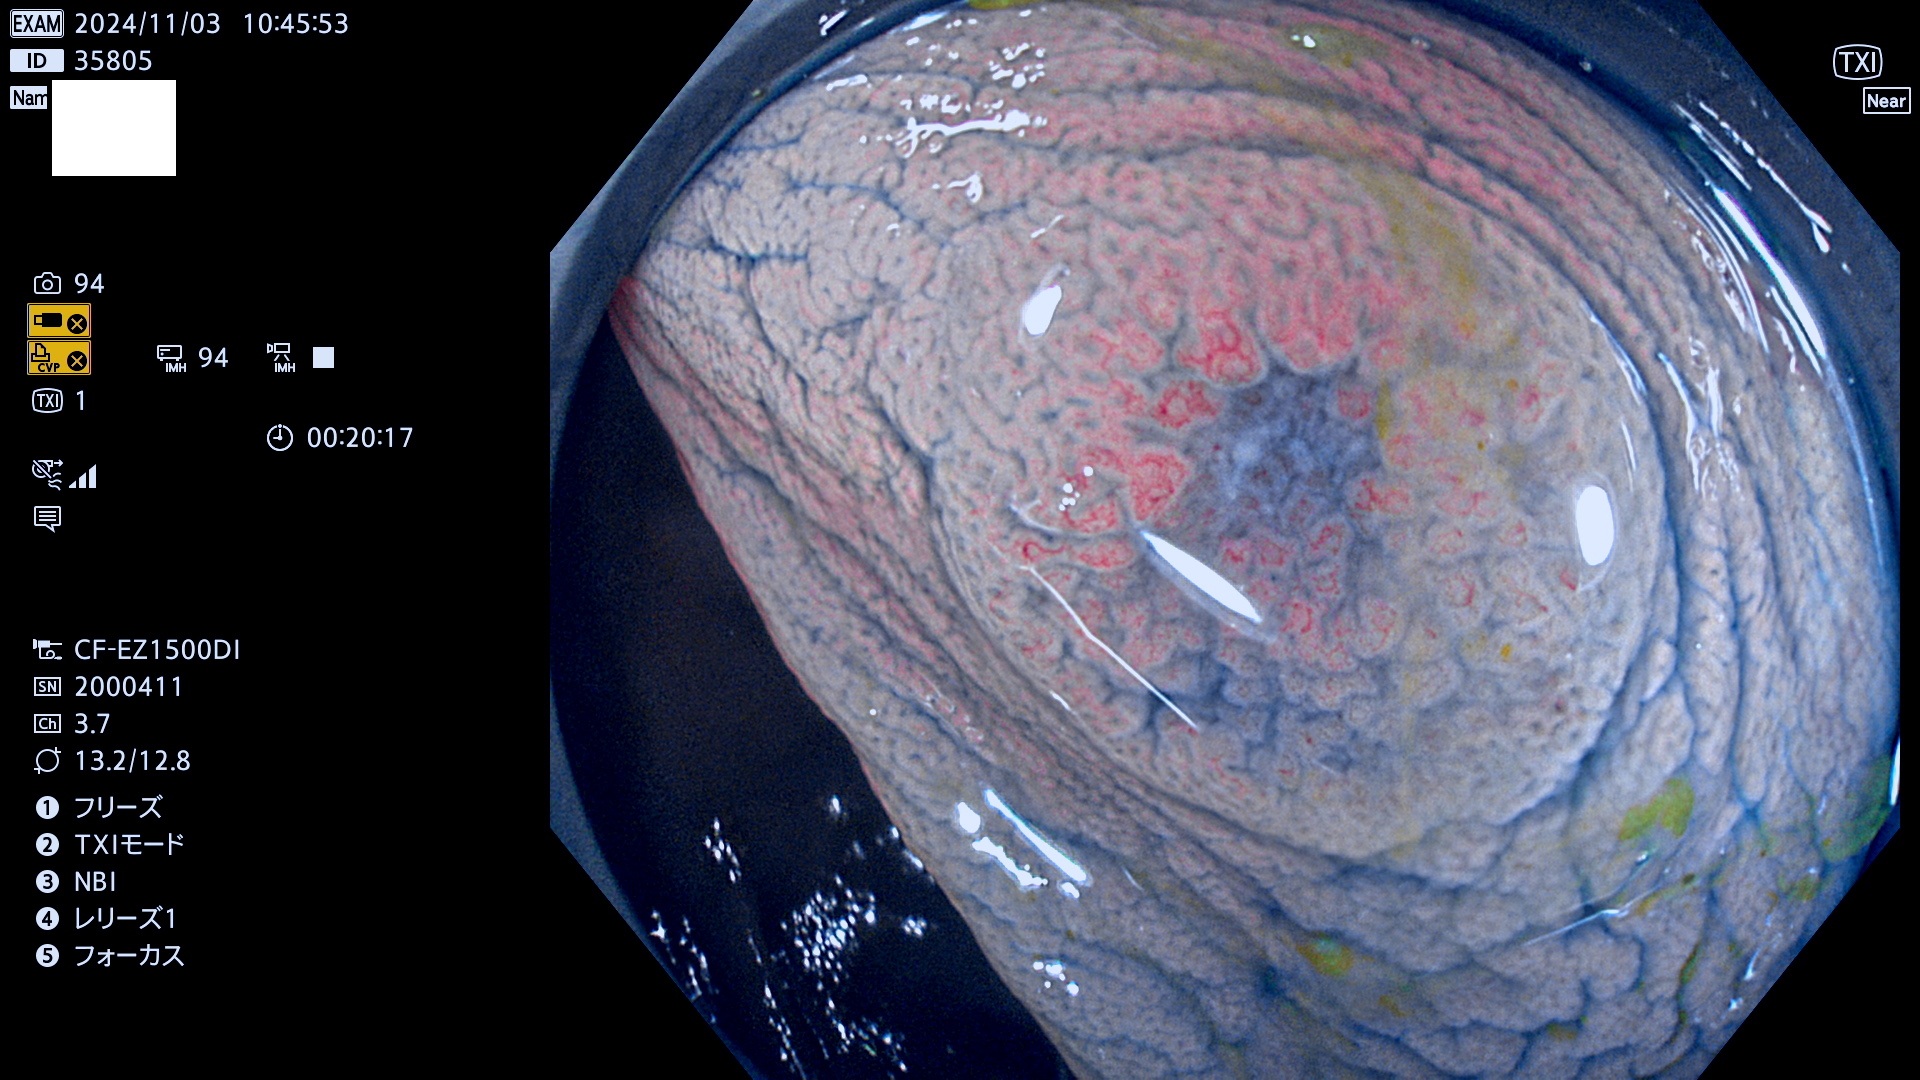

完全に平坦な物をUb、陥凹している物をUcと呼びます。最も発見が難しく危険な病変です。

毎週の検査(木・金・土・日)に発見されたUb、Uc型・腺腫を、その週の日曜の夜にUPし1週間、提示します。

抽出の対象期間 2024年10月31日〜11月3日の4日間(48件の検査)7件 (7/48=15%)